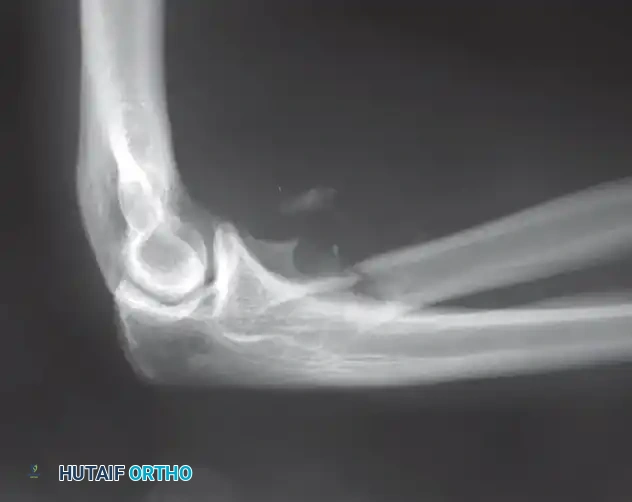

Distal Humerus and Elbow Reconstruction

When tumors involve the distal humerus, resection often requires sacrifice of the collateral ligaments and the articular surface of the elbow. Reconstruction is typically achieved using a linked, semi-constrained total elbow arthroplasty designed for oncologic defects.